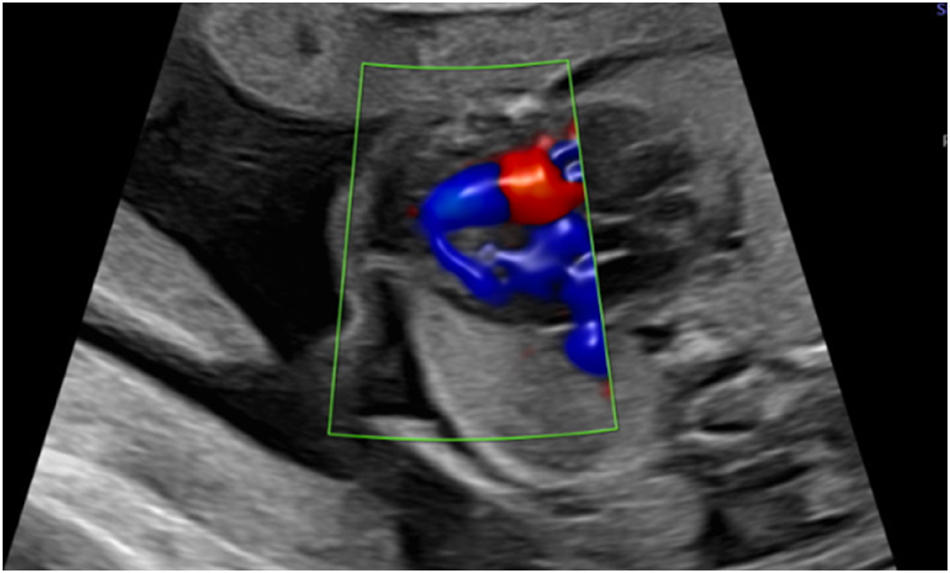

A 45-year-old woman presented for a first trimester scan with normal nuchal translucency (NT 1.77 mm) and normal sonoanatomy. The risk calculated for T18 was 1 in 4, based on low maternal serum ß-HCG and PAPP-A. NIPT was performed at mother’s request: the initial result was “the fetus is female, low risk for trisomy 18”. However, the second trimester ultrasound scan revealed a sex discrepancy. Invasive diagnostics were again recommended but declined. Repeat NIPT at 21 weeks showed a high risk of trisomy 18 and a male gonosomal constitution. In addition, a ventricular septal defect (VSD) (Figure 1), hypoplasia of the thymus and clenched fists (thumbs) were suspected at follow-up ultrasound. Amniocentesis finally confirmed a mosaic trisomy 18 with karyotype: mos47,XY,+18[22]/46,XY[18].

Apical ventricular septal defect in 26 weeks.